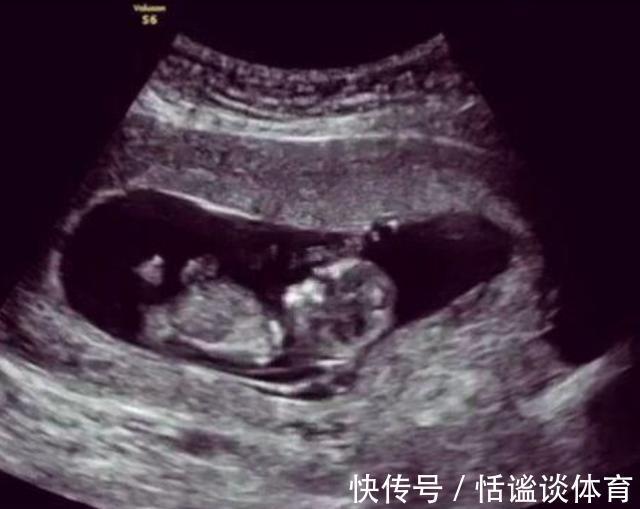

准爸妈|孕期38周却“胎死腹中”,这些“孕妇杀手”要预防,准爸妈得留意

对于家庭来说,如果女性怀孕了,那么绝对是头等大事,家里的人都会盼望着孕期能够顺利孕育出一个健康的小宝宝来,但是怀孕的过程中随时都有可能出现意外,尤其是怀孕的初期,随时都可能出现胎停育的情况,虽然谁都不想看见这样的情况,但是在优胜劣汰的自然环境面前,谁也不能改变什么。

一门心思的研究怎么生育一个健康的宝宝,还不如在孕期中研究下如何保证腹中胎儿能健康发育来的主要,更要注意的是腹中胎儿的心跳,别像下面这对小夫妻一样。

案例小吕和妻子结婚后日子就过得非常的和美,在别人的眼里他们就是模范夫妻的典范,在结婚后不久妻子就怀孕了,小吕也是非常的激动和开心,并且在日常生活中对于怀孕的妻子更是无微不至的照顾着,每一次妻子做产检,小吕都要亲自去陪伴。这天小吕又要陪着妻子去医院产检,头天晚上俩人还在一起数着胎动畅想着孩子的模样和未来,结果到了医院,门诊护士在给妻子听胎动的时候神情变得非常的紧张,还让旁边的护士赶紧去叫来了主治医生,然后就推着妻子进入了手术室,小吕知道情况不妙,可能是妻子和孩子出问题的。

小吕一直在产科的手术之外焦急的等待着,过了很长时间,妻子的主治医生终于出来了,小吕马上上前询问妻子和孩子的情况“医生,我的妻子和孩子怎么了?她们怎么样了?”医生回答说“现在胎儿的状态不是很好,需要引产,你赶紧准备一下并且办理下住院手续吧。”小吕当时就懵了,妻子再有2周就是预产期了,怎么却突然要引产了呢?

分析医生做引产的时候,发现胎儿并没有出现脐带绕颈的情况,并且胎位什么的也很正常,但是为什么胎儿就没有了心跳呢?在做完手术后,妻子被推回了病房,夫妻俩面面相觑都是一脸愁容,家里还放着一堆为孩子准备的东西,但是现在孩子却胎死腹中了,这样的事情换了谁肯定都是很难接受得了的。但是没有办法,就算是现在医疗水平如此高,对于“胎死腹中”的事情依然是没有任何办法解决不了,甚至都没有答案,一个新的生命就这么戛然而止了。

很多准爸准妈一定都想知道,引起胎儿停止发育的情况都和什么有关系?根据医学上的相关数据来看,在怀孕期间,胎儿突发性出现心跳停止的情况,多半是和染色体出现异常有关系,而且大多是母体原因较多。造成胎儿在孕早期胎停的原因也有很多种,像染色体异常、基因突变,还有就是准妈妈接触到化学品、烟酒等。